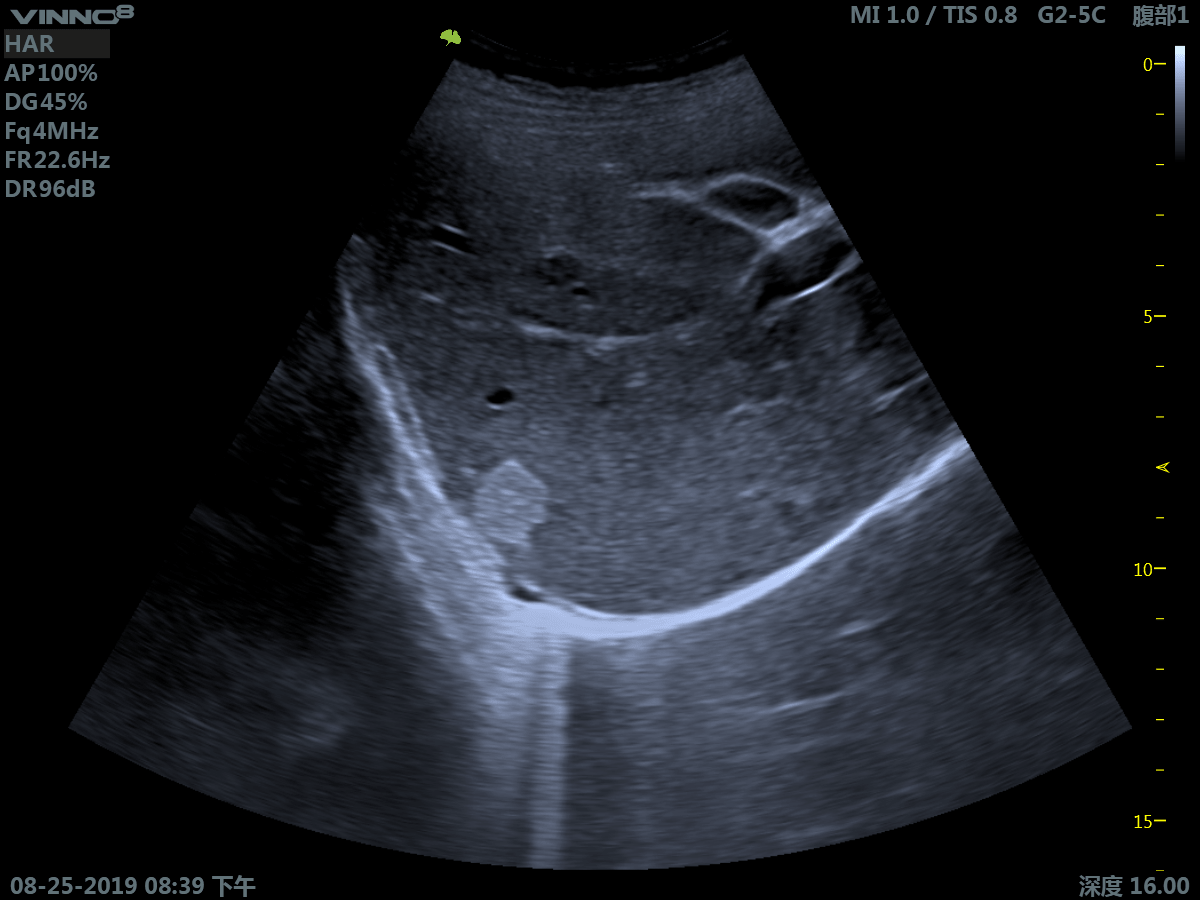

Клиническое применение:

- брюшная полость

- инновационная платформа RF обеспечивает суперчистое изображение в результате сверхвысокой скорости обработки данных

3. Режим тканевой гармоники - технология выделения гармонической составляющей колебаний внутренних органов, вызванных прохождением сквозь тело базового ультразвукового импульса.